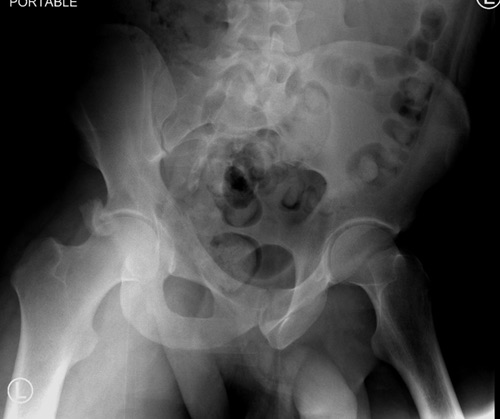

Дискуссия показывает интересные стороны развития тактики лечения переломов вертлужной впадины. Для разработки лечебной тактики сперва надо установить диагноз, и разбор показывает, что не все справляются с такой задачей! Изучение перелома надо начать из стандартных снимков: для переломов костей таза: прямой, inlet и outlet, а для перелома вертлужной впадины - снимки по Judet.

В последнее время, из-за красоты участился показ 3D снимков, хотя надо начать c обычных, и, по необходимости, компьютерная томография с 3D! Без головки бедра 3D покажет общую картину и вовлечение сустава, а более детально только в срезах КТ.

Данная картина показывает очень редкий перелом передней колонны, но перед операцией еще раз надо просмотреть обещанные дополнительные КТ срезы.

Представленные слайды Александром из Севастополя, имеет ценность, но, кроме inlet, остальные стандартные Judet рентген снимки должны показать правоту принятого решения. Возможно, здесь фиксация перелома вертлужной впадины, но по рентгену трудно понять!